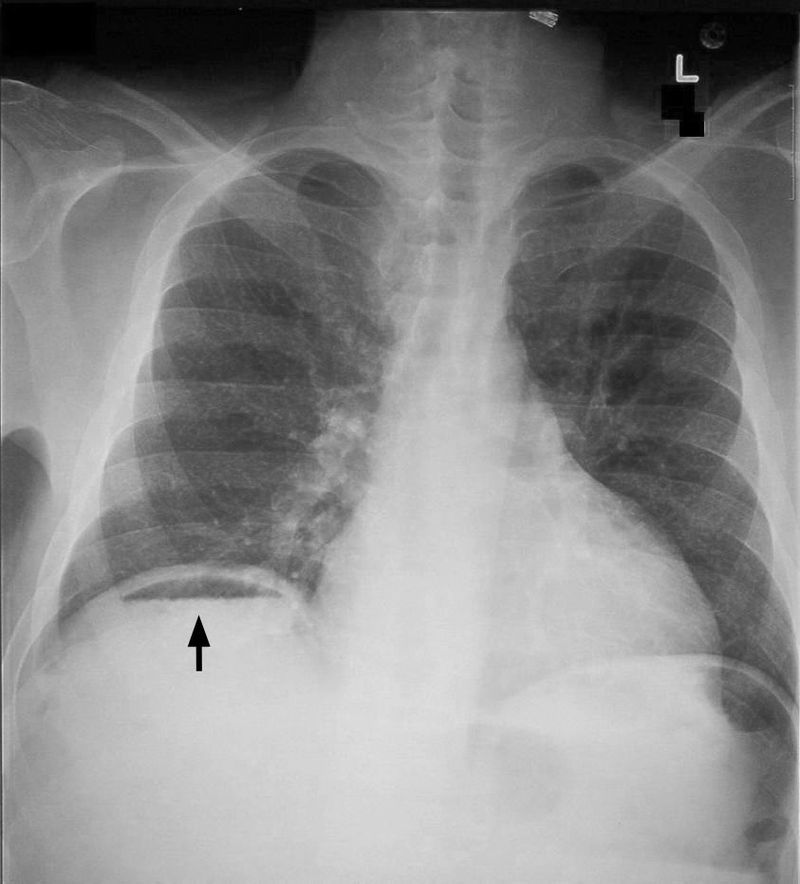

What may a CXR of Peritonitis show?

Gas under diaphragm

(aka Pneumoperitonuem)